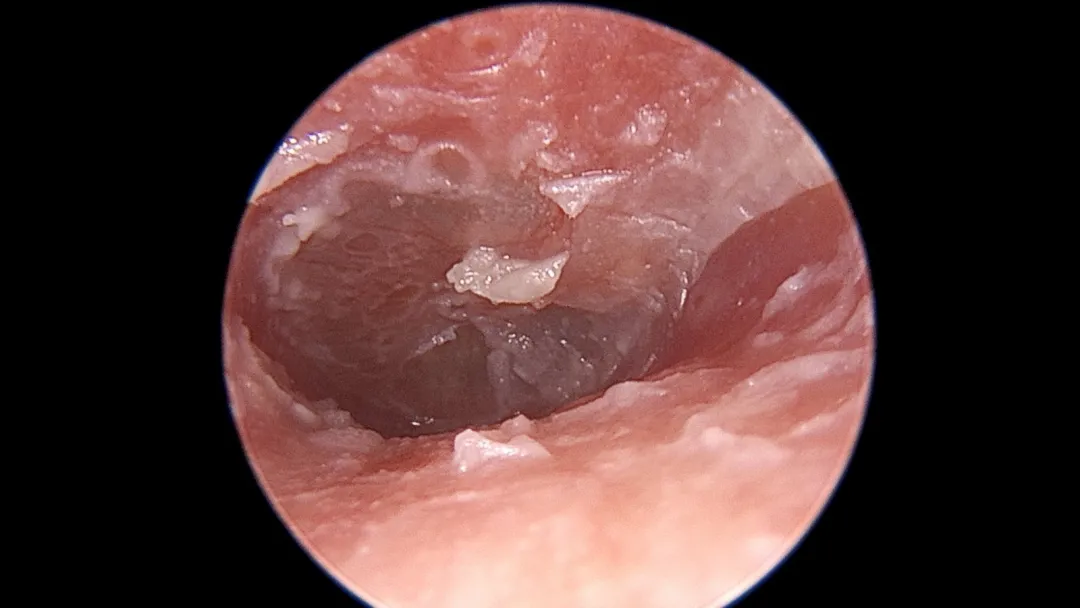

专业的说法叫:霉菌性外耳道炎,也就是真菌感染。

致病的真菌种类很多,常见的有以曲霉菌、念珠菌、青霉菌及毛霉菌。

程度轻的能看到一些霉丝和霉点,严重的可能会有一些脓性分泌物。

这时候,在你看不到的地方,耳朵可能就已经变成了这副“病入膏肓”的样子——